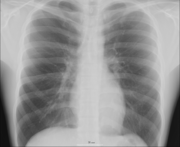

Human anatomy, physiology and biochemistry are complementary basic medical sciences, which are generally taught to medical students in their first year at medical school. Human anatomy can be taught regionally or systemically; that is, respectively, studying anatomy by bodily regions such as the head and chest, or studying by specific systems, such as the nervous or respiratory systems. The major anatomy textbook, Gray's Anatomy, has recently been reorganized from a systems format to a regional format, in line with modern teaching methods. A thorough working knowledge of anatomy is required by all medical doctors, especially surgeons, and doctors working in some diagnostic specialities, such as histopathology and radiology.